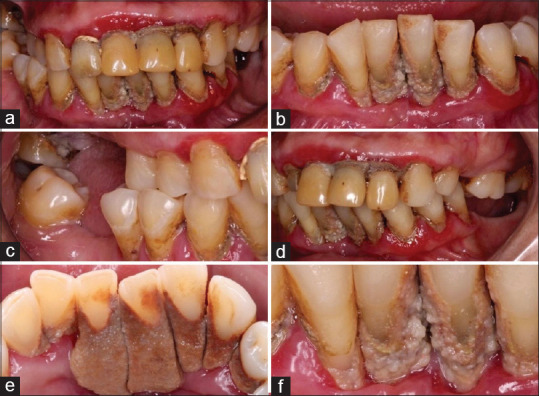

机会性感染在获得性免疫缺陷综合征中感染人类免疫缺陷病毒(HIV)的患者中很常见。本病例报告显示了一个患有牙周炎、艾滋病毒/丙型肝炎合并感染和念珠菌病的个体的临床病例,使用不同的药物并接受不规则的抗逆转录病毒治疗。几种局部和全身性疾病的结合突出了该病例的重要性以及卫生专业人员在艾滋病毒感染背景下了解这些综合病理管理的必要性。我们可以得出结论,由于与这些病理相关的致病机制,牙医了解艾滋病毒感染患者的牙周病是极其重要的。

Opportunistic infections are common in patients infected with human immunodeficiency virus (HIV) in acquired immunodeficiency syndrome. This case report demonstrates a clinical case of an individual with periodontitis, HIV/hepatitis C coinfection, and candidiasis, using different drugs and under irregular antiretroviral therapy. The combination of several local and systemic conditions highlights the importance of the case and the need for health professionals to know the management of these combined pathologies in the context of HIV infection. We can conclude that it is extremely important for dentists to be aware of periodontal diseases in HIV-infected patients, due to the pathogenic mechanisms associated with these pathologies.